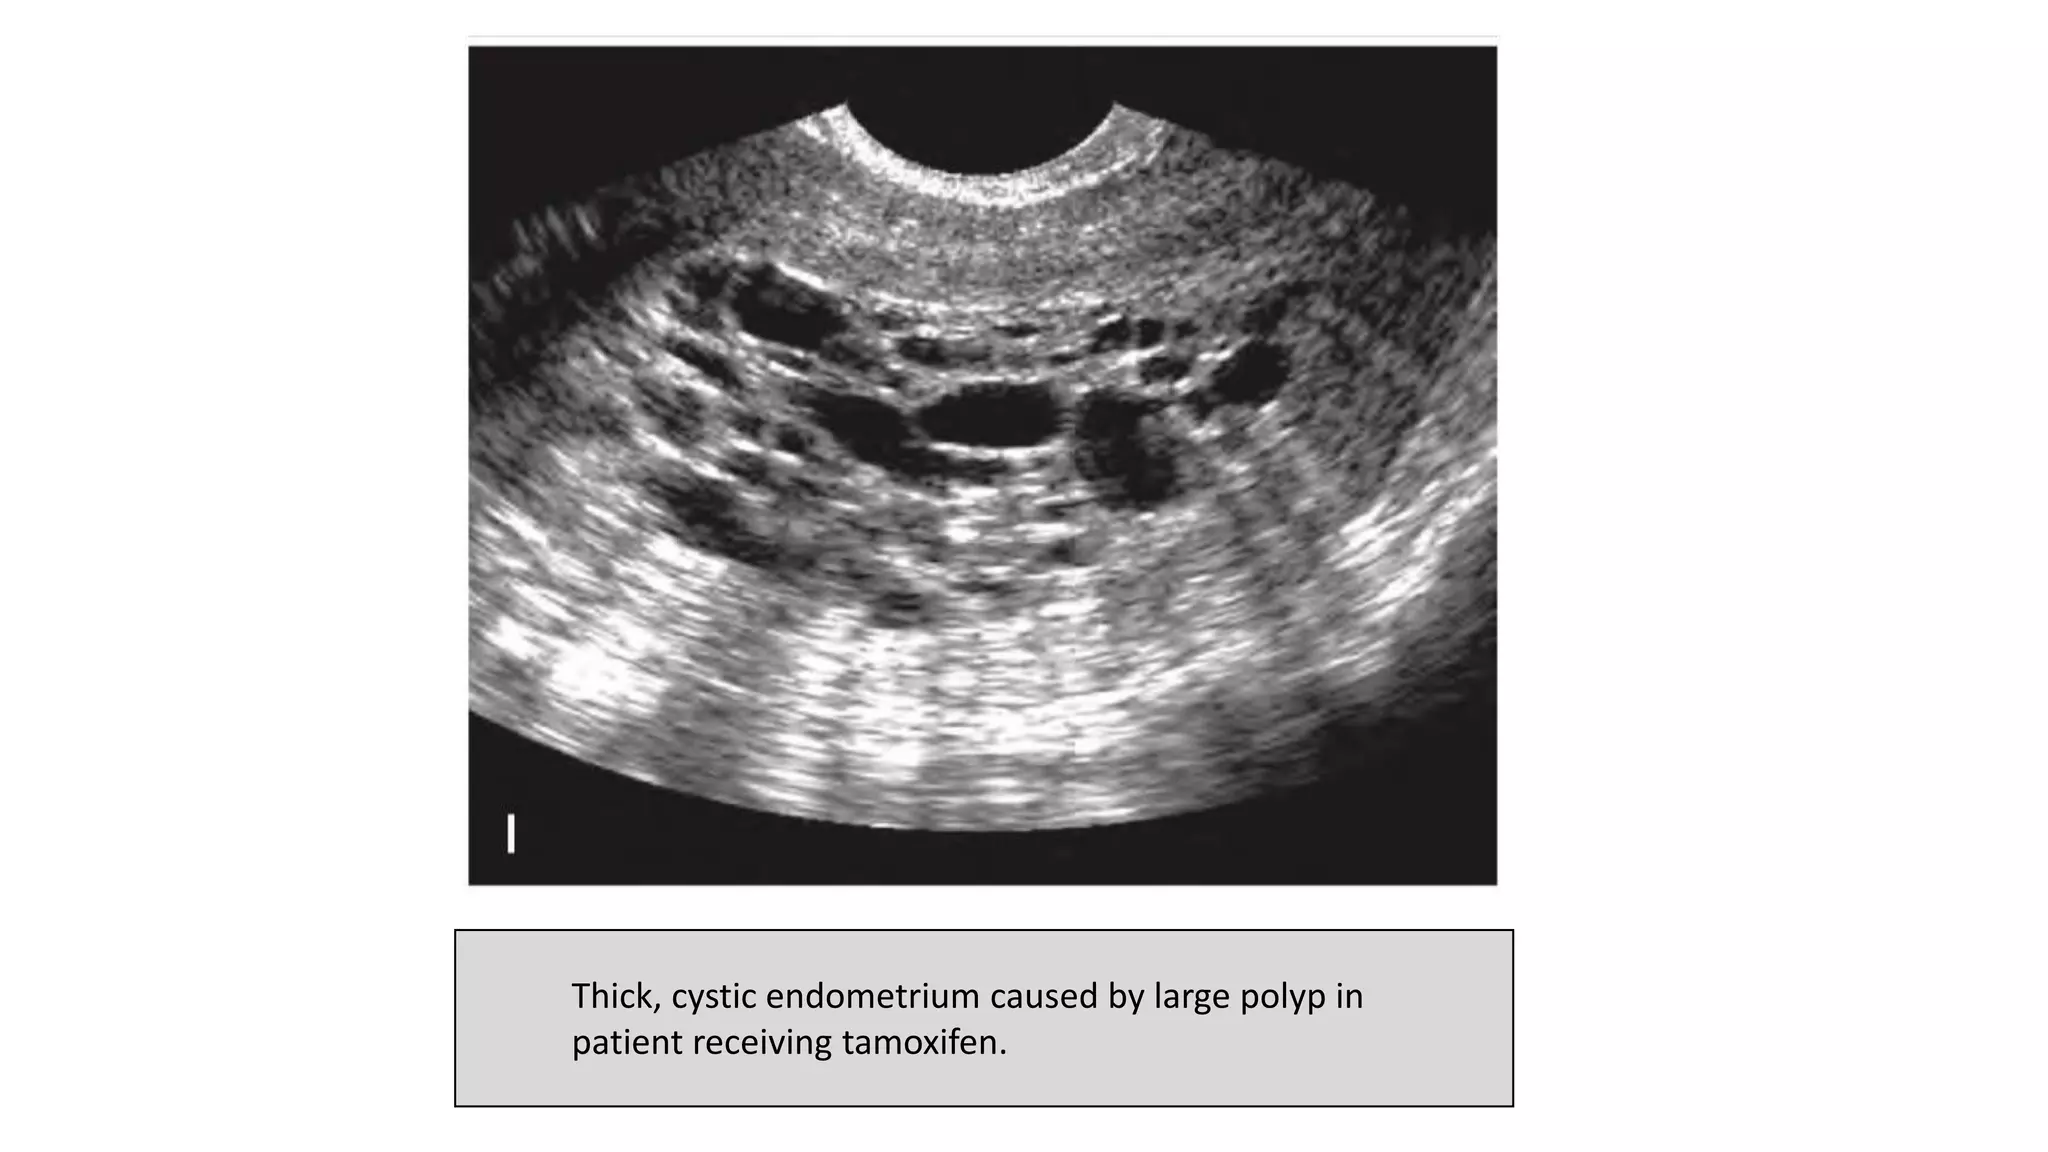

• On sonography

-Tamoxifen-related endometrial changes are nonspecific and similar to

those described in hyperplasia, polyps, and carcinoma.

-Cystic changes within the thickened endometrium are frequently seen

-Polyps are frequently seen.

-A correlation exists between increased endometrial thickness and

duration of tamoxifen therapy longer than 5 years.

• In some patients taking tamoxifen, the cystic changes actually have

been shown to be subendometrial in location and represent

abnormal adenomyosis-like changes in the inner layer of

myometrium.

• Because it may be difficult to distinguish the endometrial-myometrial

border in many of these patients, sonohysterography is valuable in

determining whether an abnormality is endometrial or

subendometrial.

Thick, cystic endometrium caused by large polyp in

patient receiving tamoxifen.